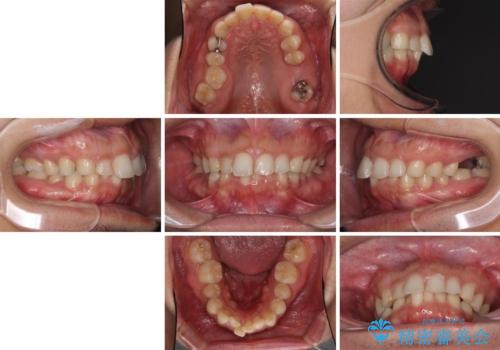

- 深い咬み合わせと前歯のデコボコ、奥歯の欠損を気にして来院された患者様です。

歯列矯正はインビザラインを使用し、矯正治療中の適切な時期に奥歯の欠損部位にインプラントを埋入することとしました。